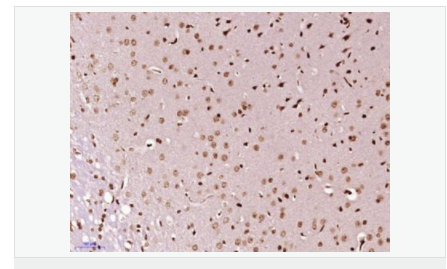

細(xì)胞定位細(xì)胞核

產(chǎn)品介紹Zinc finger protein-like 1 is a 310 amino acid single-pass membrane protein with two zinc fingers at the N-terminus, the second of which is likely a RING domain. The RING domain, which is a 40-60 amino acid, cysteine-rich domain that binds two atoms of zinc, plays a key role in the ubiquitination pathway. The presence of zinc finger-like and leucine zipper-like domains in ZFPL1 suggests a role in DNA binding and transcriptional regulation. ZFP1 is widely expressed in the golgi apparatus and is involved in maintaining golgi structure and regulating the rate of cargo transport.

Required for cis-Golgi integrity and efficient ER to Golgi transport. Involved in the maintenance of the integrity of the cis-Golgi, possibly via its interaction with GOLGA2/GM130.

Subcellular Location: